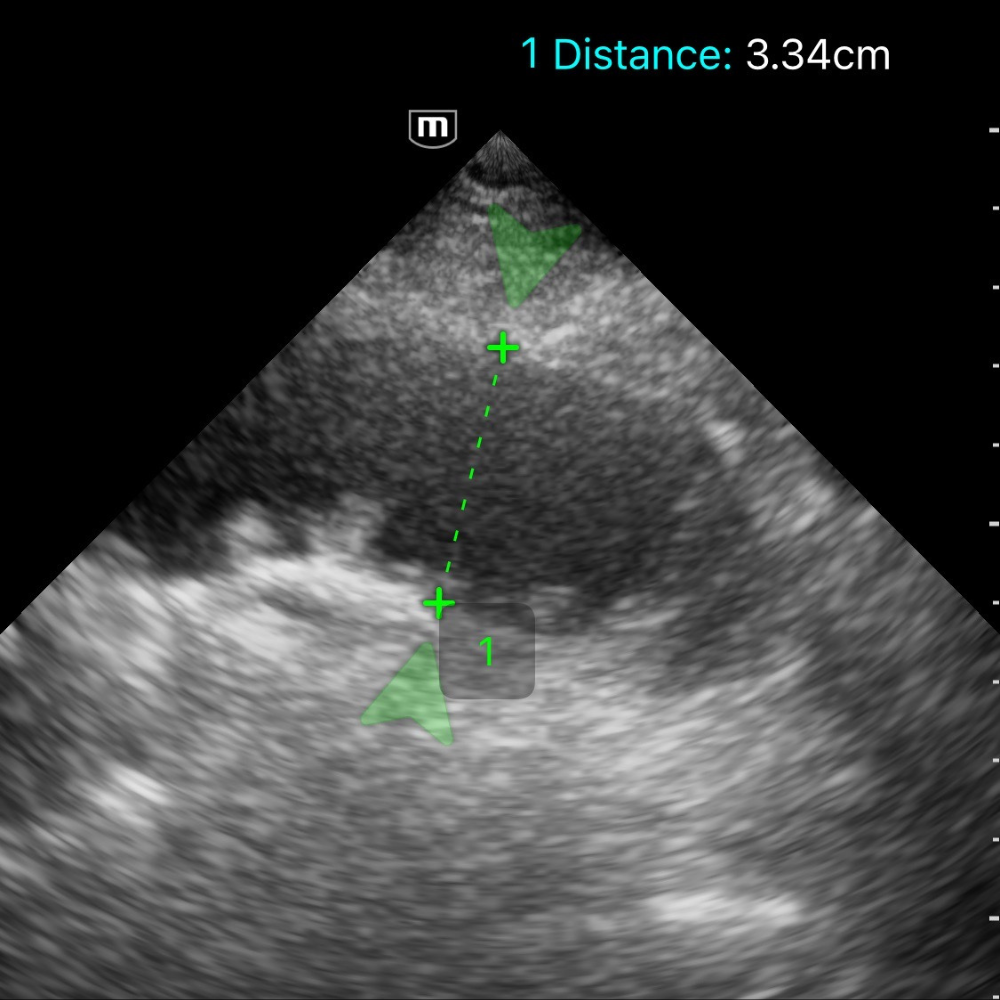

- Dilatation des anses grêles : diamètre > 25 mm (> 2,5 cm), contenu liquidien, paroi fine.